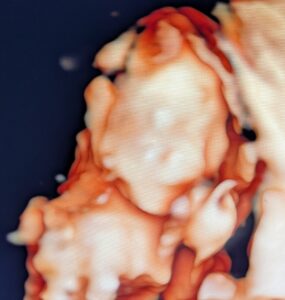

検査の最後の方には4Dエコーもしてくれました!12週はまだまだ小さいため(頭からお尻までの長さが約5cm)経腹エコーからだとなかなか鮮明に見えなかったのですが、先生から

すると12週なのに上の写真の通り。耳、目、鼻、口がしっかり見えました!

抵抗なければやっていただくのがオススメです。

そして12週ですが性別も分かりました!ほとんど男の子で確定だろうとのことでした。

検査終了後、4Dエコー(画面では肌色でしたが印刷物は白黒)と通常のエコー写真と検査結果の紙をもらえました。